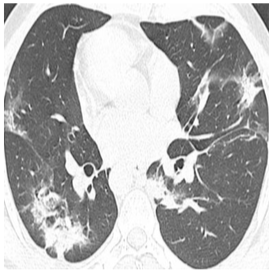

Until now, Coronavirus SARS-CoV-2 has caused more than 850,000 deaths and infected more than 27 million individuals in over 120 countries. Besides principal polymerase chain reaction (PCR) tests, automatically identifying positive samples based on computed tomography (CT) scans can present a promising option in the early diagnosis of COVID-19. Recently, there have been increasing efforts to utilize deep networks for COVID-19 diagnosis based on CT scans. While these approaches mostly focus on introducing novel architectures, transfer learning techniques, or construction large scale data, we propose a novel strategy to improve the performance of several baselines by leveraging multiple useful information sources relevant to doctors' judgments. Specifically, infected regions and heat maps extracted from learned networks are integrated with the global image via an attention mechanism during the learning process. This procedure not only makes our system more robust to noise but also guides the network focusing on local lesion areas. Extensive experiments illustrate the superior performance of our approach compared to recent baselines. Furthermore, our learned network guidance presents an explainable feature to doctors as we can understand the connection between input and output in a grey-box model.